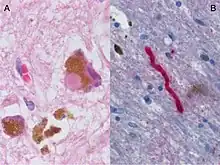

- Parkinson's disease (PD) is a neurodegenerative disease resulting from the apoptosis of dopaminergic neurons in the central nervous system, especially the substantia nigra, as well as heightened response to the excitatory neurotransmitter, glutamate (i.e., excitotoxicity).[12] While the most obvious symptoms are related to motor skills, prolonged progression of the disease can lead to cognitive and behavioral problems as well as dementia. Although the mechanism of apoptosis in the brain is not entirely clear, speculation associates cell death with abnormal accumulation of ubiquitinated proteins in cell occlusions known as Lewy bodies, as well as hyperstimulation of neuronal NMDA receptors with excessive glutamate neurotransmitter via the aforementioned pathway.[12] Like Alzheimer's, Parkinson's Disease lacks a cure. Therefore, in addition to lifestyle changes and surgery, the goal of pharmaceutical drugs used in the treatment of PD patients is to control symptoms and limit, when possible, the progression of the disease. Levodopa (L-DOPA), the most widely used treatment of PD, is converted to dopamine in the body and helps to relieve the effect of decreased dopaminergic neurons in the central nervous system. Other dopamine agonists have been administered to patients in an effort to mimic dopamine’s effect at excitatory synapses, binding its receptors and causing the desired postsynaptic response.[13]